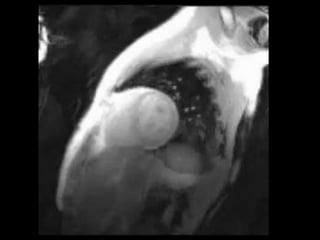

Cardiac masses

• Atrial myxoma

• left atrium (75%), right atrium (20%), or ventricles or mixed chambers

• inhomogeneous brightness in the center on cine SSFP imaging because

of its gelatinous content

• may have a pedunculated attachment to the fossa ovalis.

Cardiac masses • Protocolsequence to assess morphology, motion, perfusion, and delayed enhancement, in addition to inherent differences in T1 and T2 and abnormal physiology • benign masses - atrial myxoma, rhabdomyoma, fibroma, and endocardial fibroelastoma • Atrial myxoma • left atrium (75%), right atrium (20%), or ventricles or mixed chambers (5%) • inhomogeneous brightness in the center on cine SSFP imaging because of its gelatinous content • may have a pedunculated attachment to the fossa ovalis.